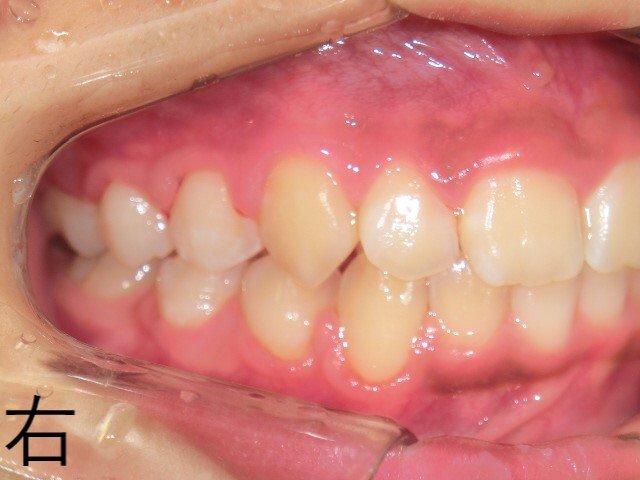

【治療終了時の咬合状態】

12歳時点で、右左ともに上下臼歯の噛み合わせが安定し、良好な咬合が確認されました。